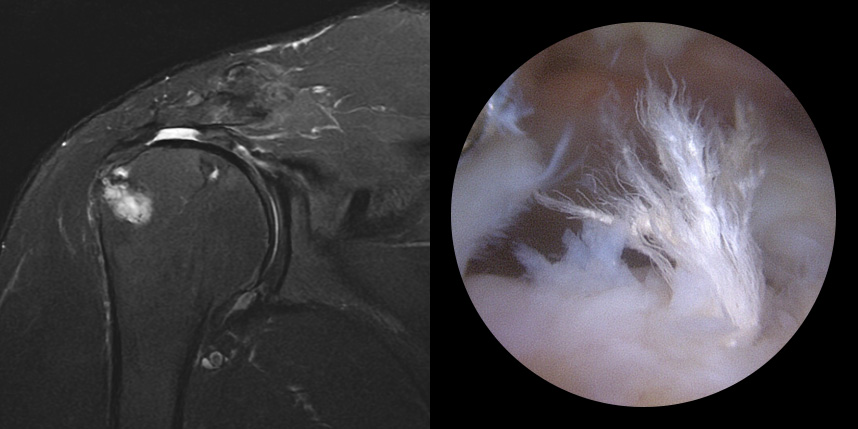

힘줄이 약할 경우 재파열에 의한 재수술

패치 보강술

* 환자에게 받은 소중한 자료입니다.